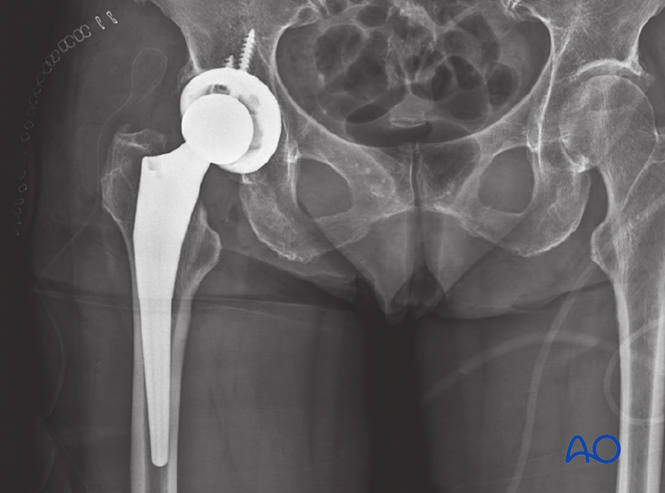

股骨颈骨折关节置换术后脱位是重要并发症。X线示例显示半髋假体脱位(左)及转为全髋假体修复(右):保留原股骨柄,移除股骨头假体,置入髋臼假体(辅以骨移植)后安装新头及衬垫。